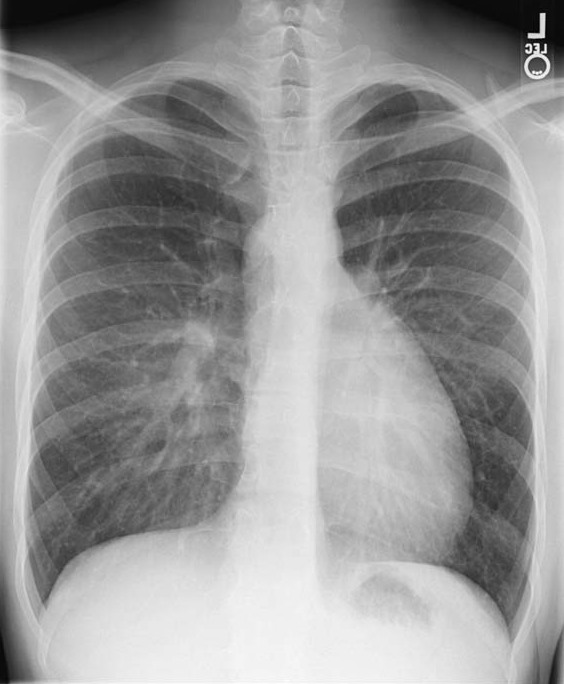

흉부 엑스레이 검사에서 대혈관 전위는 일반적으로 "실에 매달린 달걀"처럼 보이는 심장-종격동 윤곽을 보여준다. 심장 비대는 옆으로 누인 달걀을 나타내고, 상부 종격동의 좁아진 위축된 흉선은 실을 나타낸다.[4]